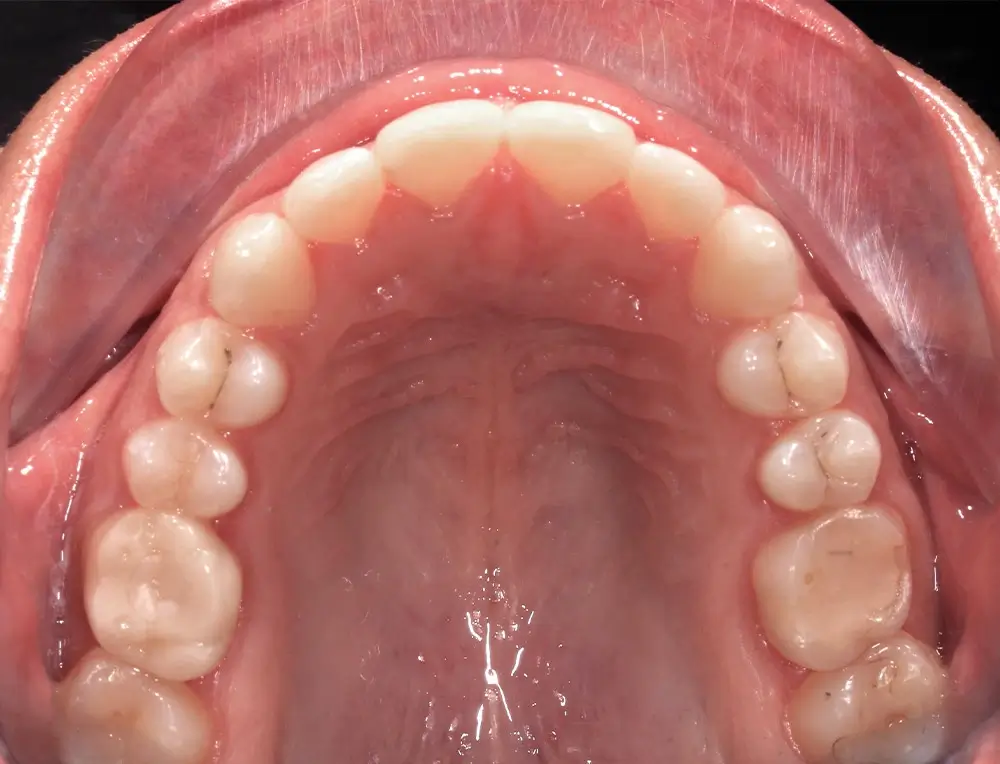

Открытый прикус - Кейс 4

Эффективность устранения дефекта прикуса посредством элайнеров FlexiLigner.

25

Количество кап НЧ

Количество кап ВЧ

Результаты лечения